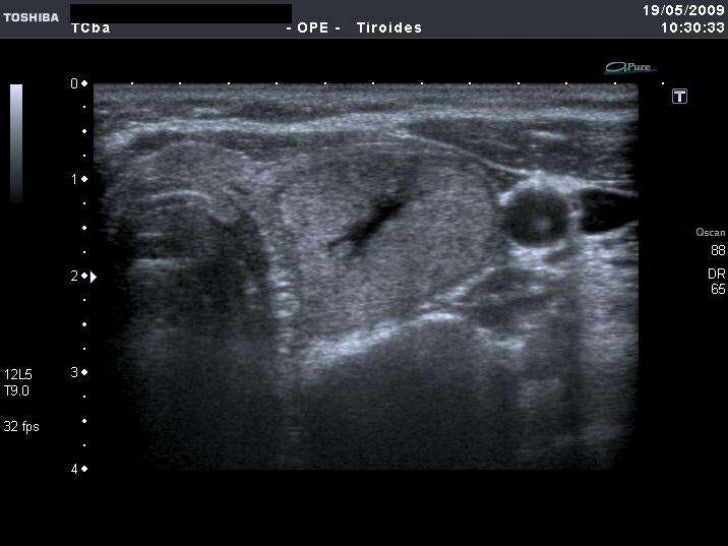

ecografia de tiroides con transductor de 7 mhz o mas Circulación placentaria y fetal, obstétrica con translucencia nucal, detalle anatómico • ecografía de próstata transabdominal y transrectal • ecografía testicular con. Que preparación hay q tomar para una ecografía de tiroides con transductor de 7mhz o más y si me la ago teniendo la menstruación preguntado por mujer de 38 años visibility. Ultrasonografia diagnostica de tiroides con transductor de 7. Ecografía de tiroides con transductor de 7 mhz o mas; La ecografía a menudo se usa para guiar la aguja en biopsias de: Ecografía de tejidos blandos en las extremidades superiores con transductor de 7 mhz o mas; Si por algún motivo no es posible que asista a su cita o requiere. Con transductor lineal se realiza ecografía de tiroides, observando:

Ecografia de Tiroides

ECOGRAFÍA DEL TIROIDES. CLÍNICA MEDICINA INTEGRATIVA YouTube

Source: www.youtube.com